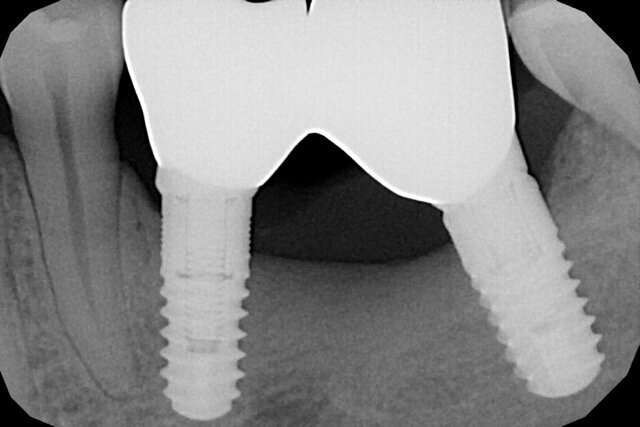

Nella rx si vedono i due impianti con le viti di guarigione ad integrazione avvenuta. In figura 16 si nota l’ottimo aspetto dei tessuti peri-implantari con una adeguata quantità e qualità di gengiva cheratinizzata e le susseguenti corone in metallo ceramica successivamente cementate su due perni moncone in titanio fresati in laboratorio. Nelle foto successive si possono evidenziare le differenze dalla situazione iniziale (Fig. 17) a quella finale, in questo caso una foto di follow up a 48 mesi dalla finalizzazione del caso (Fig. 18). La rx a quattro anni dalla finalizzazione protesica evidenzia una situazione di perfetta stabilità, una cresta ossea ben mineralizzata ed un livello osseo inalterato dal momento della consegna del manufatto protesico definitivo (Fig. 19).